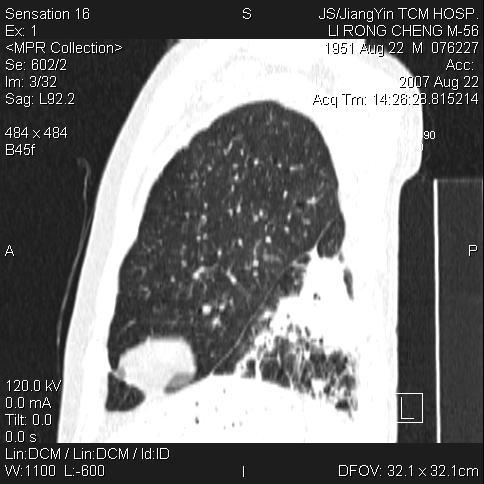

标题: CT9479:M,56Y,DM病史,咳嗽发热5天.肺脓疡.肺癌? [打印本页]

边灶边缘较光整,冠状位病灶呈大片状,,内有空洞,有胸膜反应,但无明显胸膜外侵犯征像,结合病史支持考虑肺肿脓,不排除结核,治疗后复查

好多钙化灶哦,病灶位于下叶背段,或许考虑结核更合适,做下相应检查先

考虑结核病播散!

1:病灶不是实质肿块形态,胸膜脂肪间隙存在!

2:周围有卫星病灶,不象阻塞性肺炎

3:往下间质增厚,播散征象.

支持肺脓肿,左下叶见广泛浸润,并见支扩改变。建议治疗后复查。